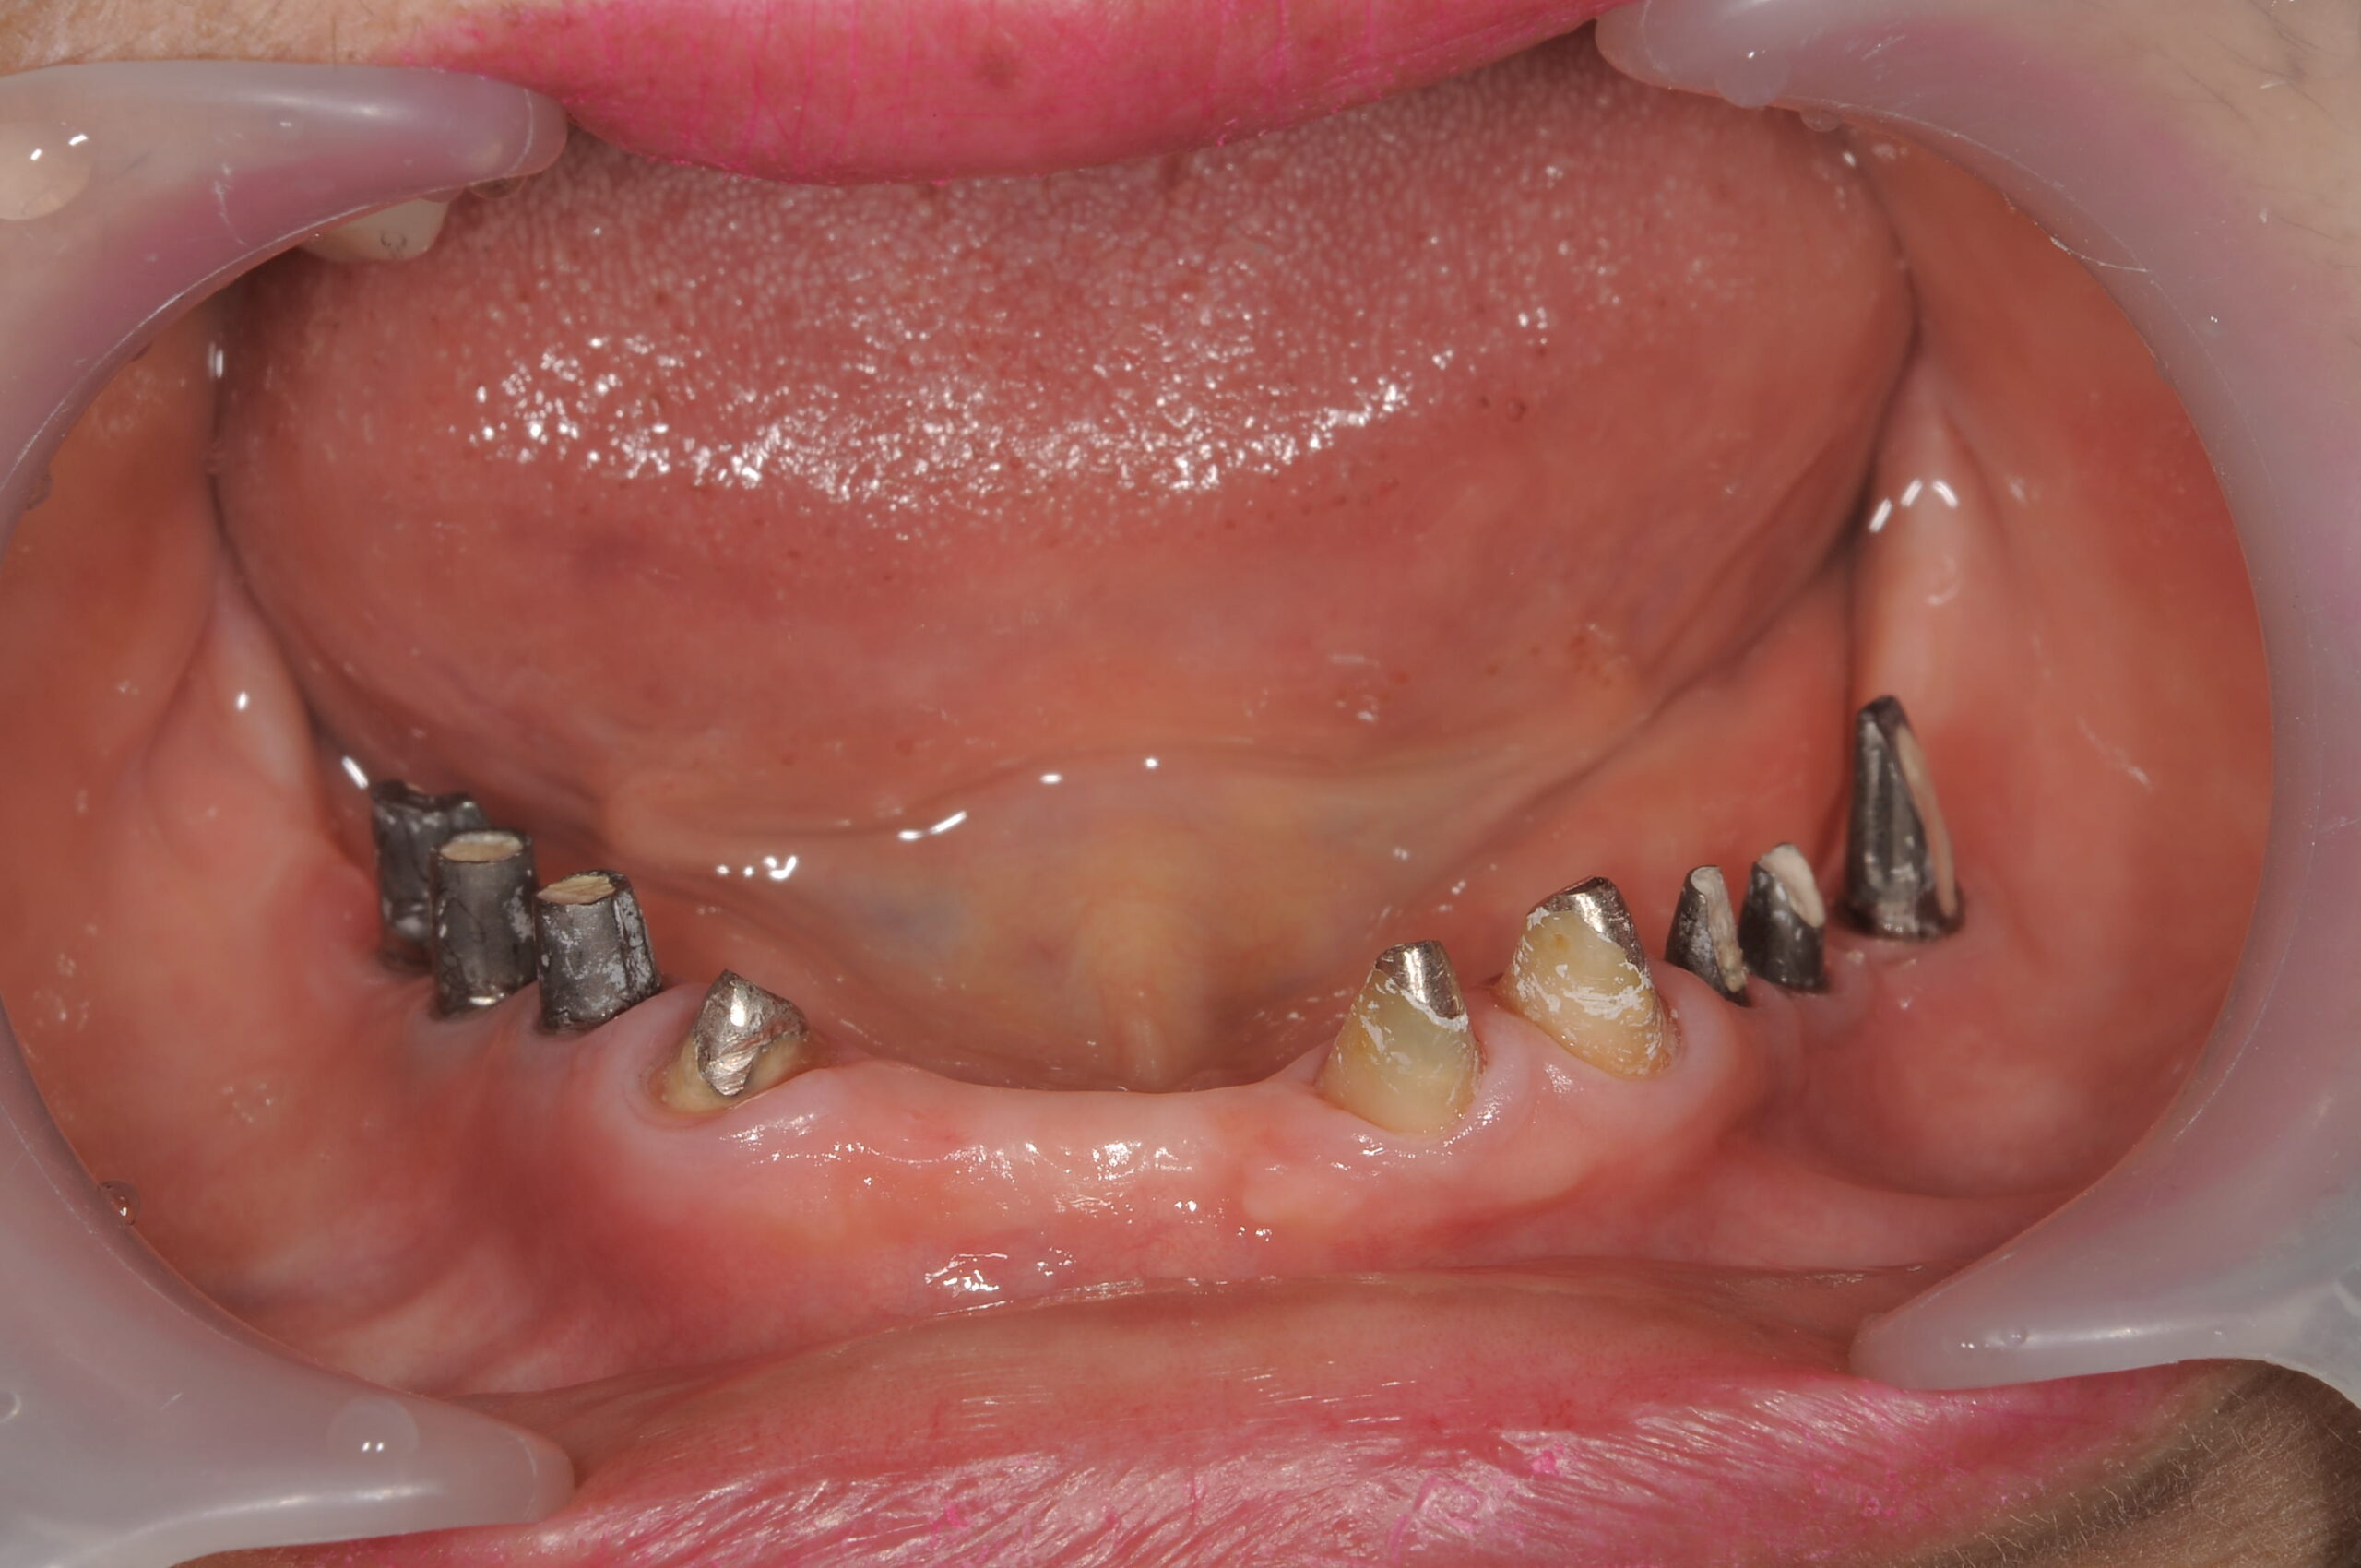

歯の数が少なく、十分に咀嚼することが難しい状態です。

下顎のインプラント埋入の状況です。

下顎管を避けてピンポイントで埋入します。